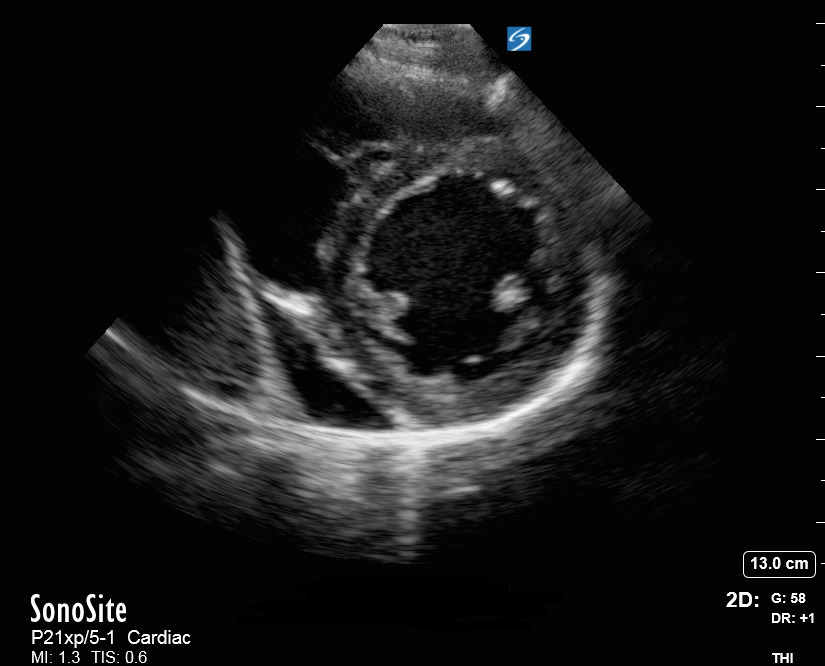

心脏胸骨旁短轴 (PSAX) 视图图像